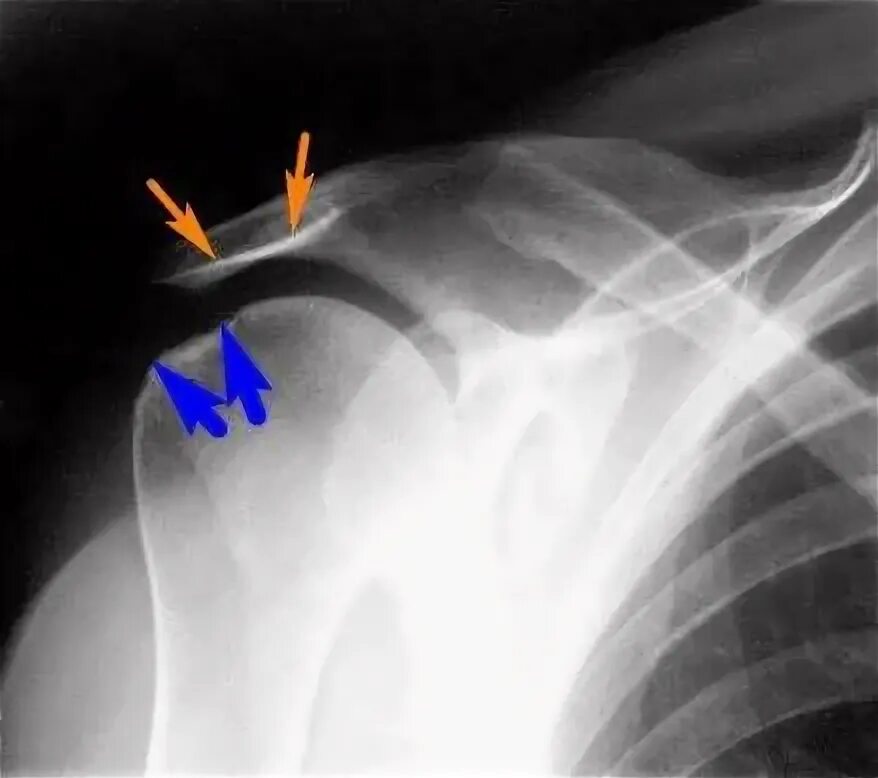

Нестабильность плечевого сустава мкб